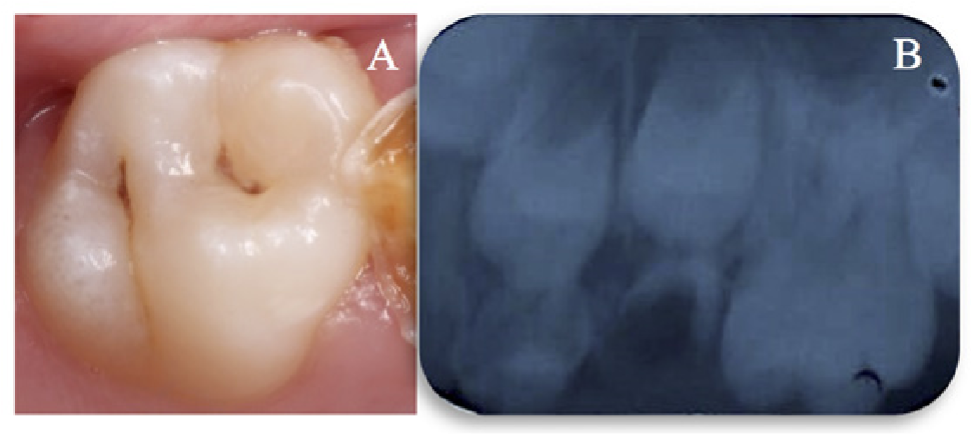

Figura 2. Aspecto clínico y radiográfico de la lesión de caries en el diente 26. A) Aspecto clínico del diente 26 que presenta una lesión de caries activa puntuación ICDAS 3. B) Radiografía periapical que muestra una imagen radiolúcida que sugiere una lesión de caries en la mitad externa de la dentina (puntuación 5) en el diente 26.

Después de 1 año, se realizó otro seguimiento, donde no se observaron cambios (Figura 4).

Figura 4. Control clínico después de 1 año. A) Diente 16; B) Diente 26.